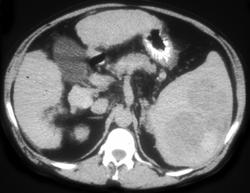

Splenic Lymphoma